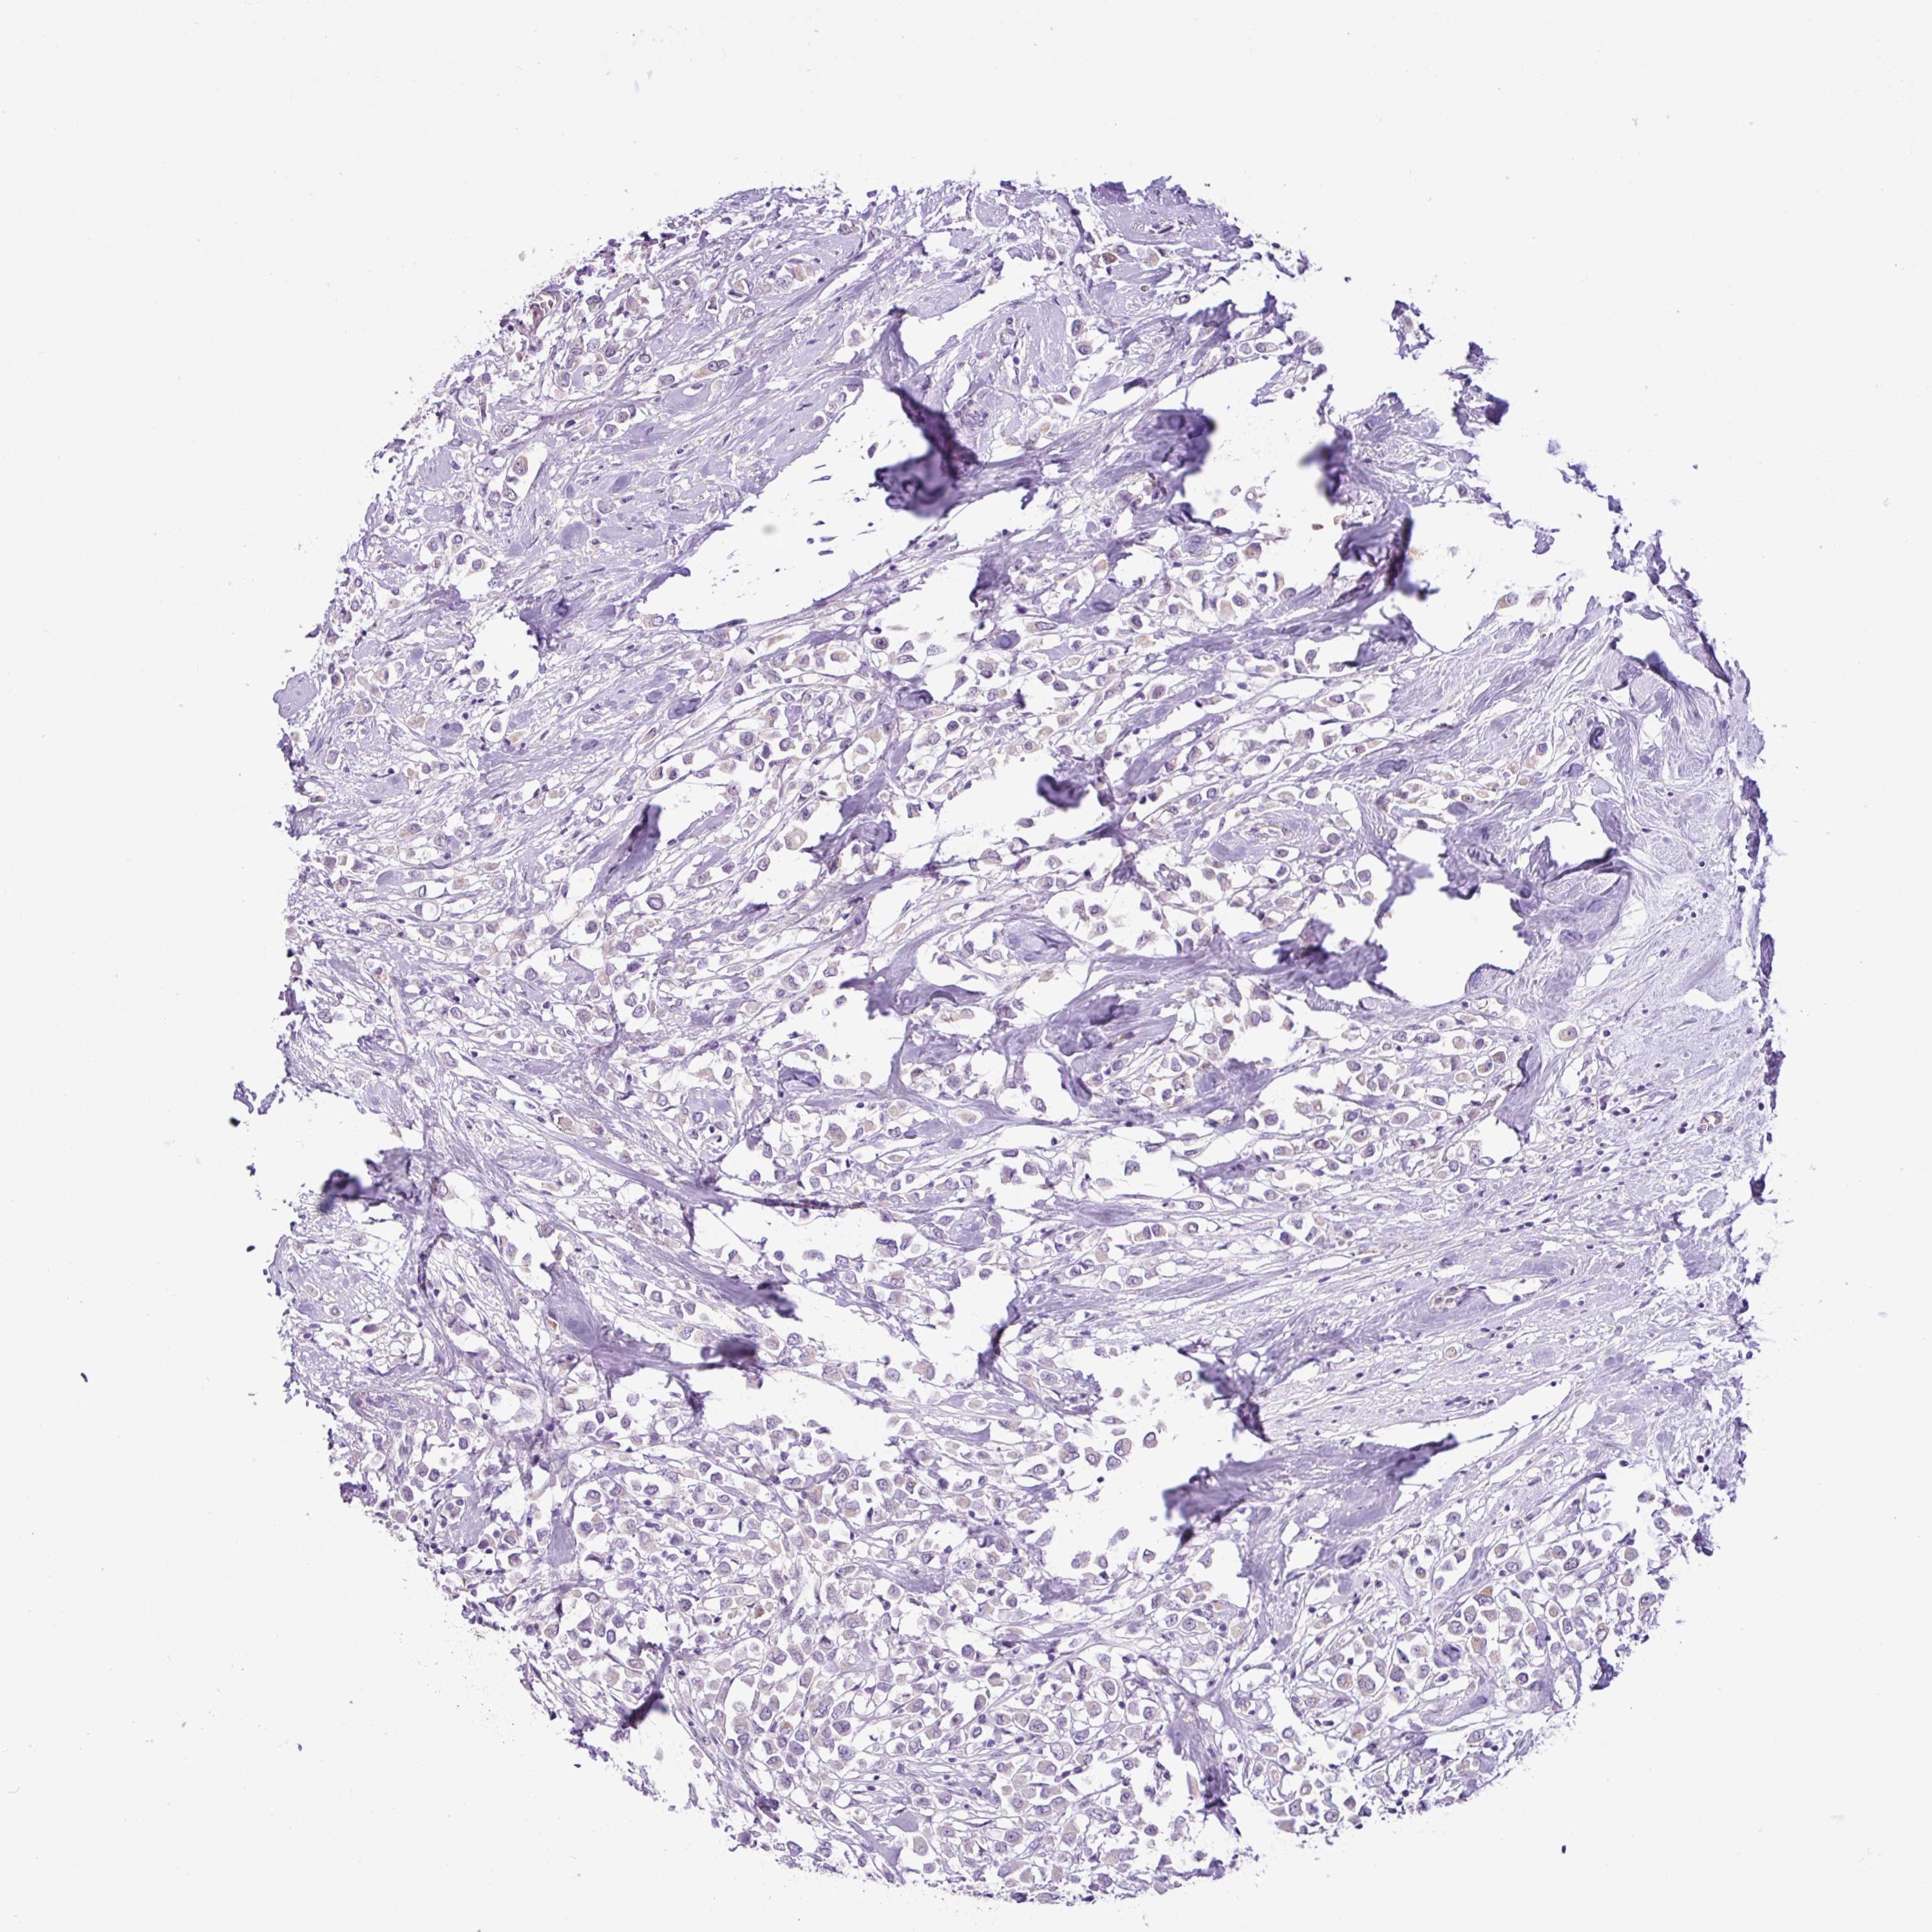

Breast cancer

Human cancer

TONSL is not prognostic in Breast Invasive Carcinoma (TCGA)